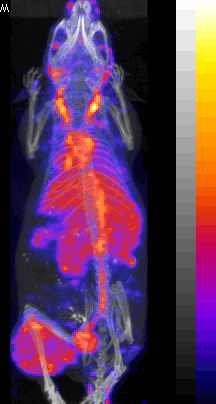

Nude mouse with a SUM190 tumor received intravenous antisense (anti-RIa)

18F-MORF/tat/Herceptin nanoparticle and PET/CT images obtained at at 3 and 8 hr.